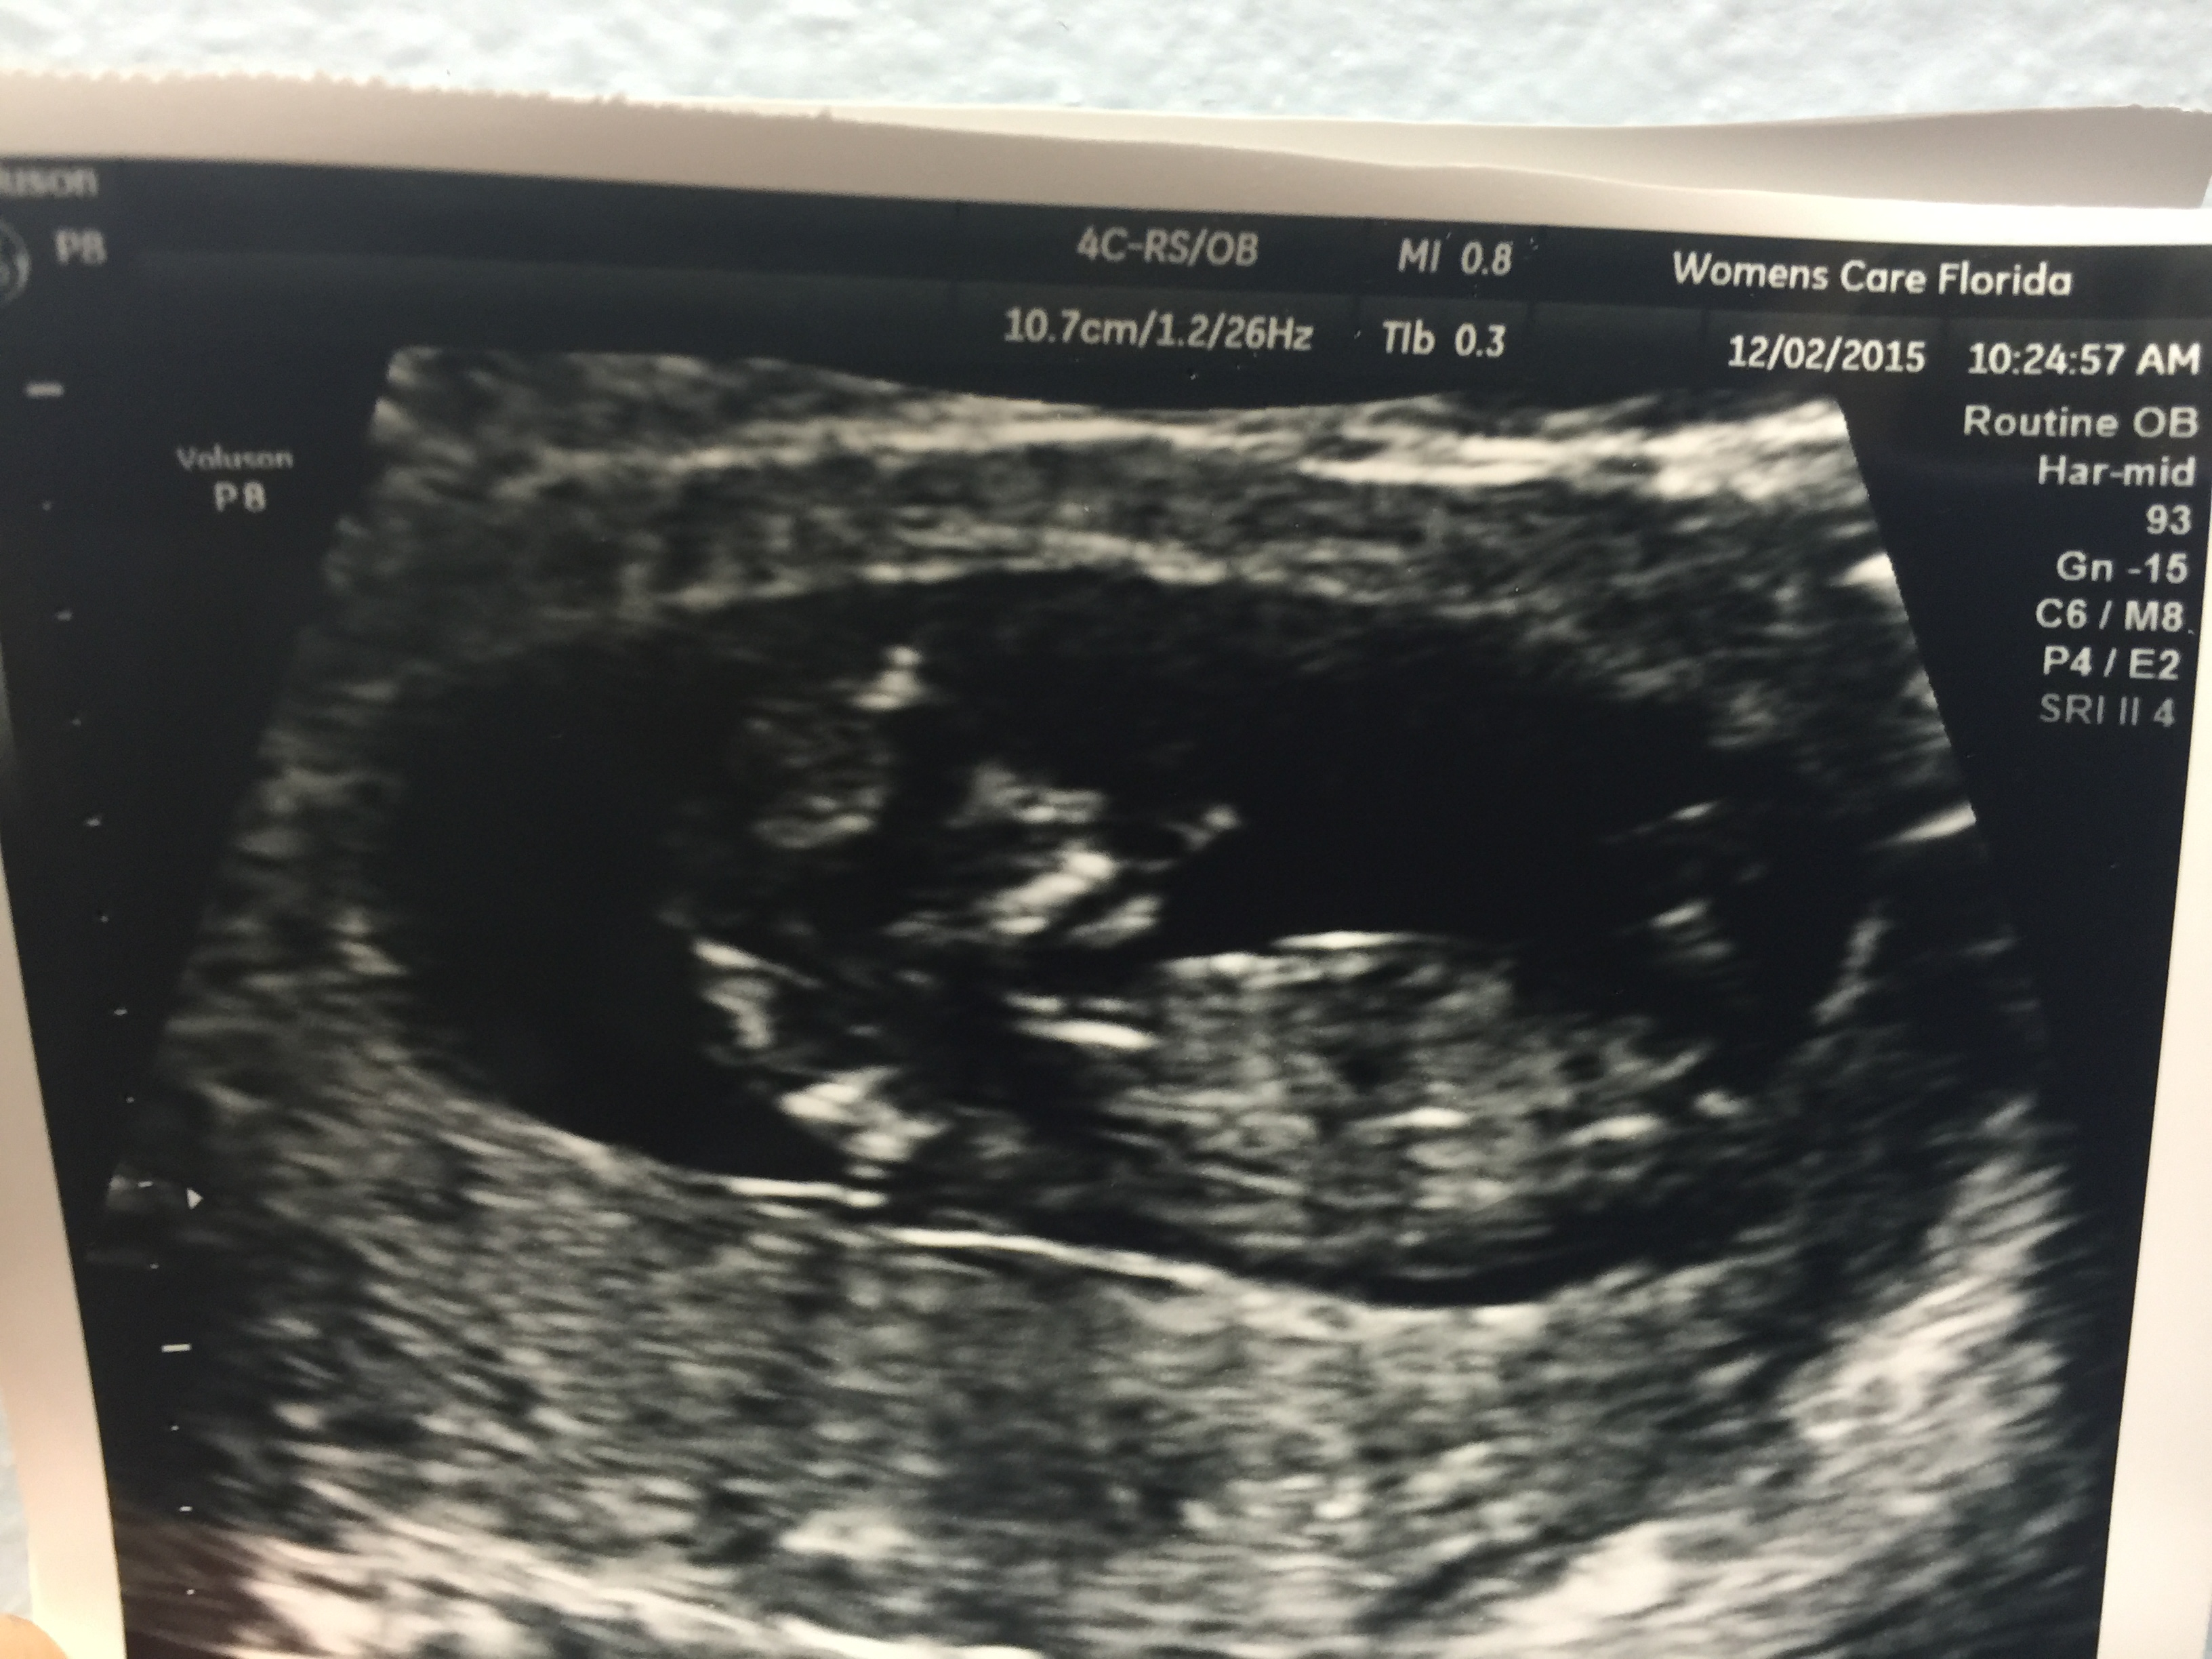

I wasn't supposed to get another ultrasound until 20 weeks but I went in today for my 12 week blood work and they couldn't find heartbeat with the Doppler. She told me not to stress and had them do a quick ultrasound to get the hr. The picture isn't too clear but beggars can't be choosers. I was grateful they printed it out for me.

I can't help but see a puppy face as the head lol. Im not seeing a penis either !